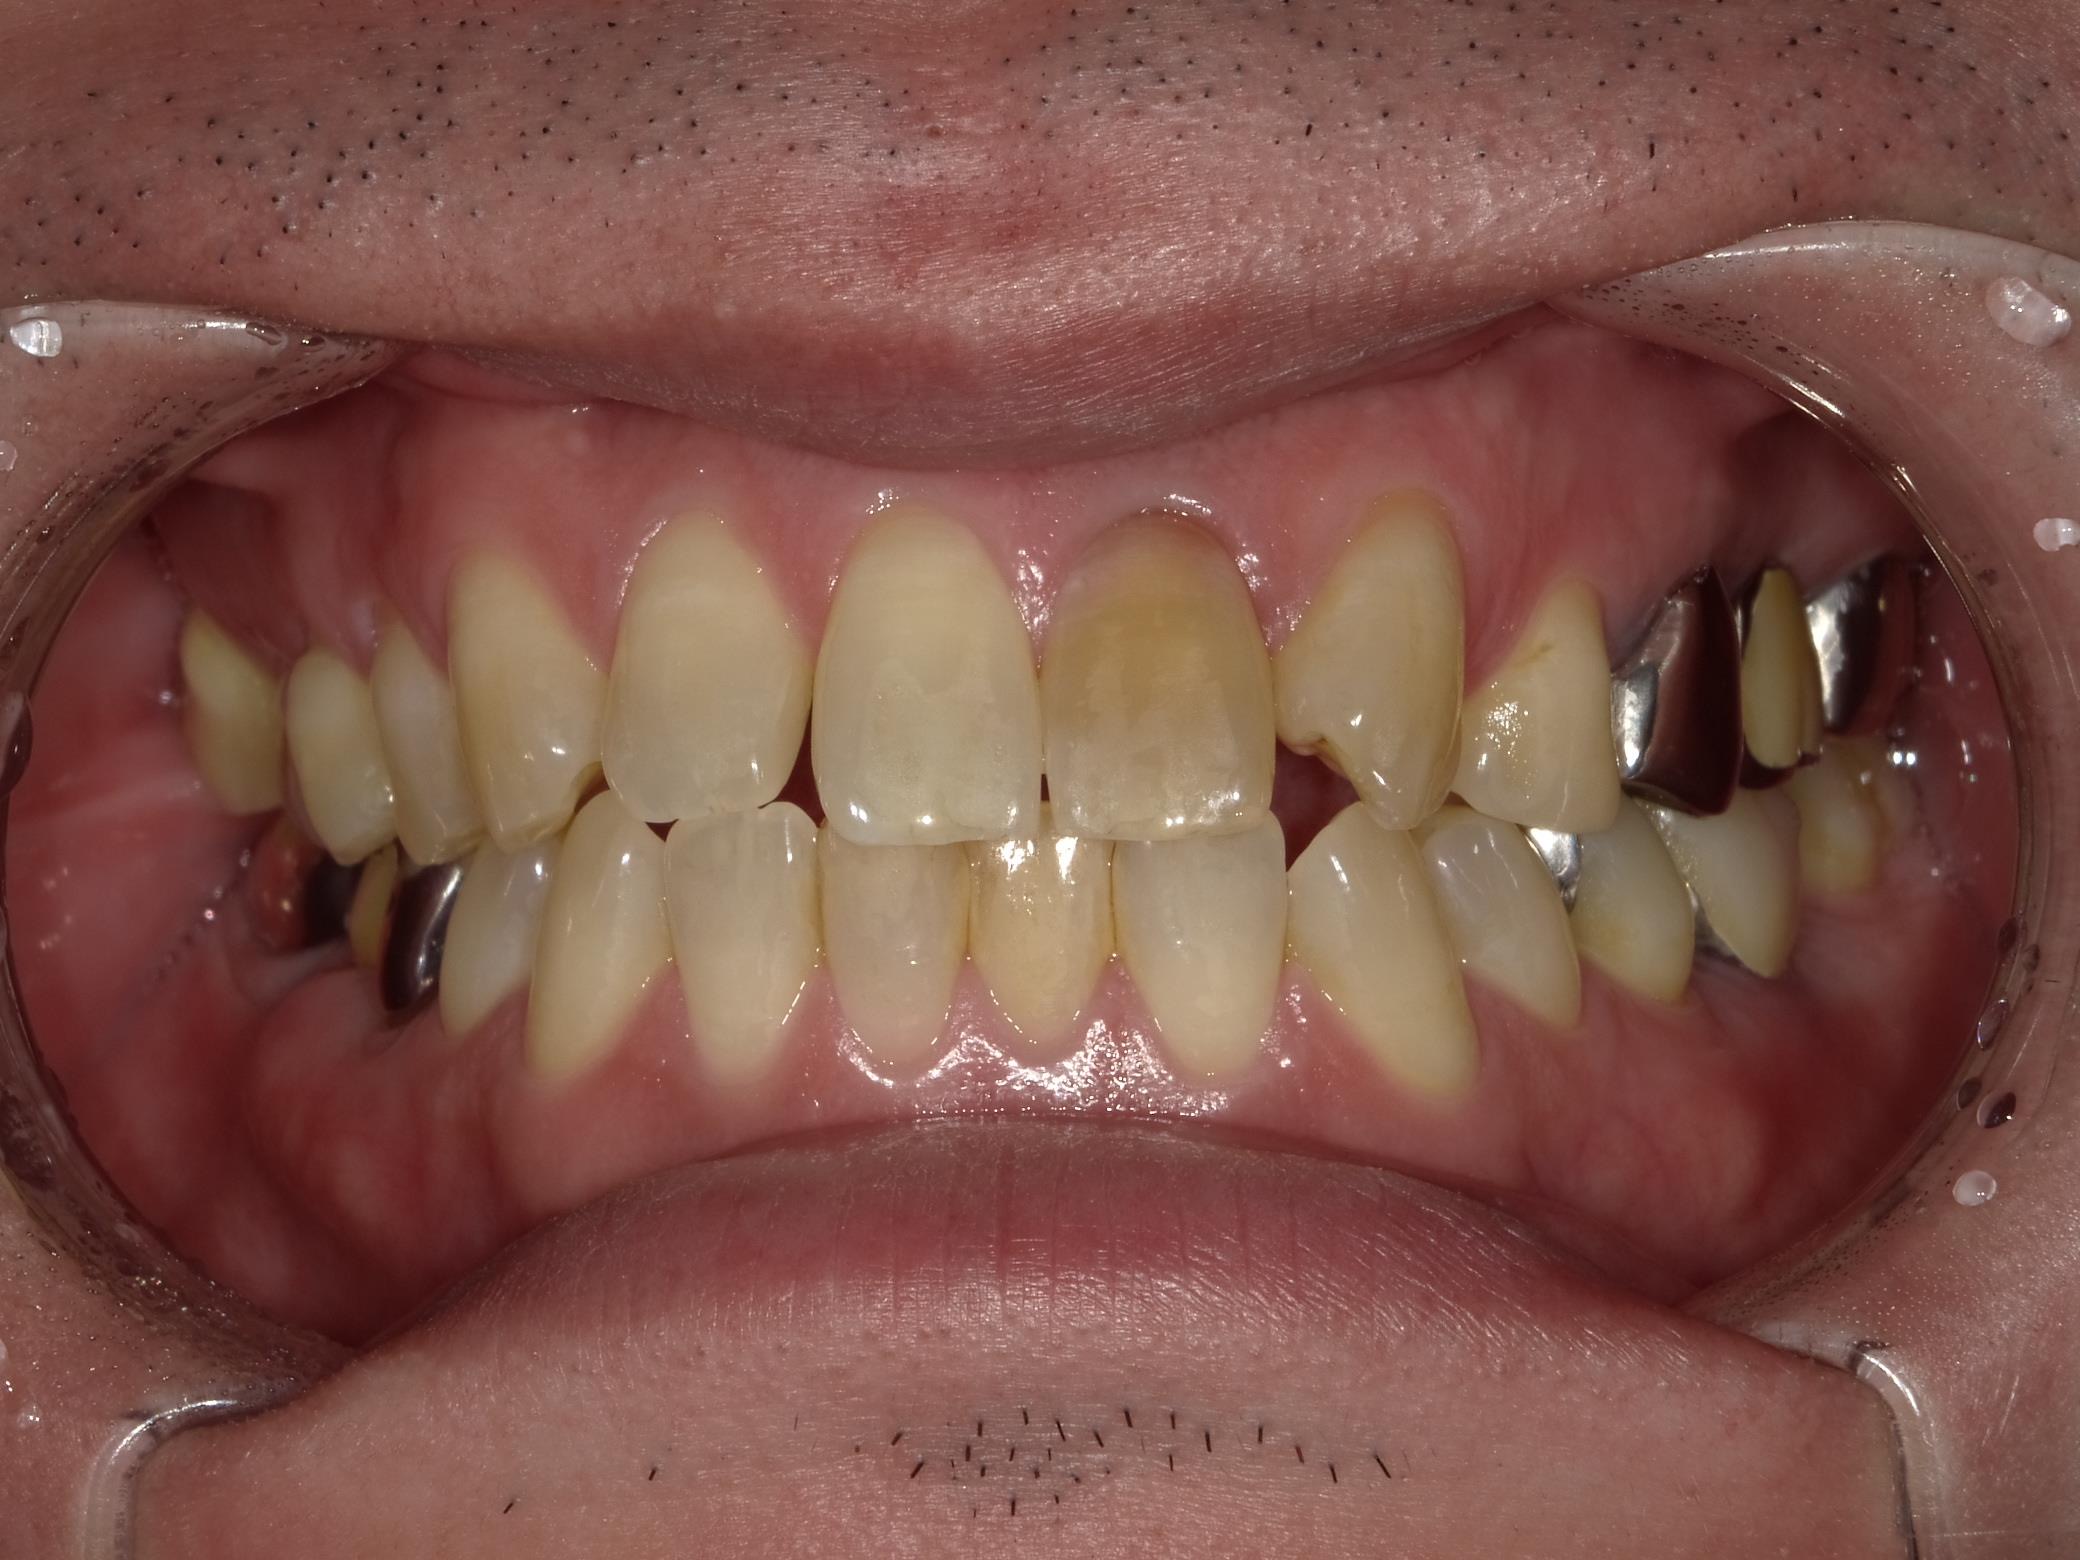

左前歯の色が違う事が気になり隣の歯と自然に馴染ませるセラミックを作る事は可能かどうかのご相談に来てくださいました。

レントゲン、口腔内写真

確かに左前歯の色だけ暗くなってしまっていますね。

おそらく根の治療を行って裏から蓋をしただけの状態のためこのように色が暗くなってしまっているのではないかと思います。

歯の神経を抜くと失活といって、神経がない状態になります。こちらを土台も立てず、被せ物をしないとこのような状態になってしまう事が多いです。

ではご説明しますね。こちらのレントゲン写真を見ていただくと左の前歯に白い線が一本入っていると思います。こちらは神経を処置した後の根充材というものが入っているんですが、根の治療が不充分に思えます。まず根の治療を綺麗にやり直し、その上にファイバーコアという土台を立て、その上にセラミッククラウンを被せるというやり方で治していきます。セラミッククラウンを作る時は両サイドの歯と完全一致するようにシェードテイキング行っていきます。